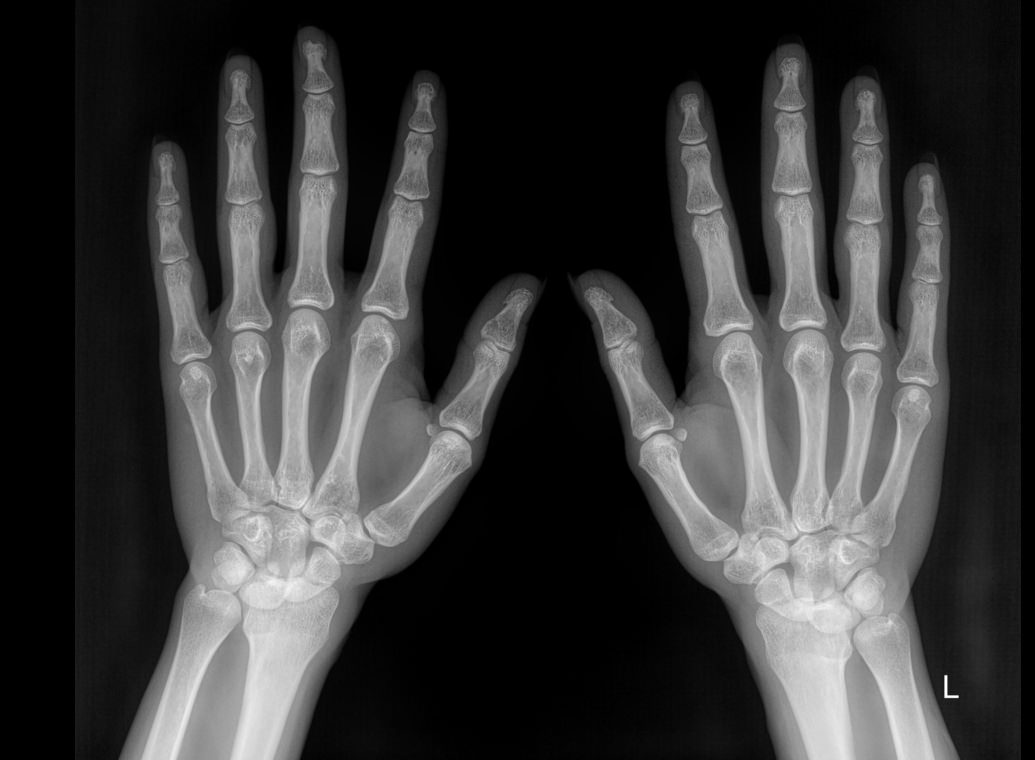

Рентген костей и суставов ― стандартная диагностическая процедура. Она основана на проникающей способности рентгеновского излучения, которое по разному задерживается в тканях разной плотности. Соответственно, изображение тканей на снимке будет в виде пятен также разных оттенков серого, от белого до практически черного. Как наиболее плотные, кости визуализируются как самые яркие. Современная аппаратура испускает минимальное излучение, составляющее минимальную часть от предельно допустимой годовой дозы.

Хронические системные патологии обычно поражают дистальные отделы верхних конечностей одновременно. Именно для этого и требуется снимок обеих кистей. В случае травмы или выявления врожденной аномалии рентгенограмма двух рук необходима для сравнения анатомических особенностей.

Что показывает рентген обеих кистей

При изучении снимка рентгенолог обращает внимание на все образования, расположенные в области кистей, но в протокол преимущественно вносит только обнаруженные патологические изменения:

• В суставных щелях;

• В соответствии суставных поверхностей друг другу;

• В структуре костной ткани и надкостницы;

• В мягких тканях.

Если будут обнаружены любые новообразования, указывает их размер и локализацию.

Диагностику выполняют без подготовки. Пациент закатывает рукава, снимает с рук все украшения, надевает защитный фартук и садится к снимочному столу. Руки на пластину детектора обычно кладут ладонями вниз и разводят пальцы, локти тоже лежат на столе. Существует и косая укладка, когда кисти кладут боком, но указания для этого должны быть в направлении.